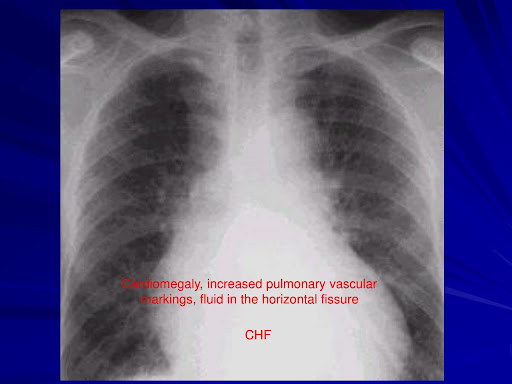

Systemic arterial supply to the normal basal segments of the left lower lobe: Typically, blood travels from the right side of your heart to the lungs through your pulmonary arteries ( pulmonary means “having to do with the lungs”). Vascular congestion or pulmonary edema is usually the result of a cardiac problem call congestive heart failure (chf).

Increased lung markings can be due to the fluid accumation or from infection. Deoxygenated blood travels through the pulmonary arteries where oxygen is taken up. Cephalization of pulmonary vascular marking can be a feature in heart failure.